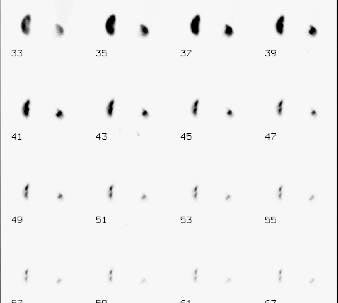

CaseTN04

- Age/Sex: 56M

- Chief Complaint: 腎移植のドナー

- Clinical Course:

- Lab. Data:

- Images:

- Tc-99m MAG3,坐位

- Blood flow

phase

- Cortical-Excretory

phase

- renogram

- DIP 10 min (左)20min

(右)立位

- X-CT:

左右の容積計測値 R/L比=0.8